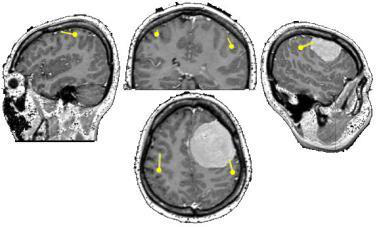

在2018年,邰慧老师因头痛、眩晕等症状,去医院检查,结果被诊断为脑膜瘤。脑膜瘤是颅内二常见肿瘤,是起源于脑膜及脑膜间隙的衍生物,大多数是良性肿瘤。国际颅底肿瘤手术教授巴特朗菲教授表示,如果将脑袋比作一个鸡蛋,颅骨相当于鸡蛋壳,脑膜就相当于蛋壳内衬的那层膜。但与鸡蛋不同的是,脑膜往往有好几层,由外向内为硬脑膜、蛛网膜和软脑膜;三层膜合称脑膜,其是重要的,主要保护人体大脑。

而脑膜上的脑膜瘤,不仅会对脑膜造成伤害,而脑膜瘤会压迫脑组织,根据其起源部位不同,受累的结构也不同,会引起相应的一些症状,如压迫到颅神经,可能引起颅神经症状,压迫视神经,可能引起视力下降,压迫嗅神经会引起嗅觉缺失,位于功能区,可能会引起肢体的偏瘫,压迫“生命中枢”脑干,还可能造成患者死亡。所以脑膜瘤即使为良性,及时治疗也是需的。

对于脑膜瘤的治疗,巴特朗菲教授表示,其优选方法手术切除。随着显微手术技术的发展,脑膜瘤的手术效果不断提高,使大多数病人得以治愈。手术的目的是切除全部脑膜瘤及其来源的膜,其手术治疗原则尽可能的切除肿瘤,同时保护周围脑组织结构与功能的完整。另外巴特朗菲教授表示,对于脑膜瘤患者来说,如果有的肿瘤比较小,或者生长在脑组织深部,就需要衡量手术的风险。如果手术风险比较大,还不如暂时观察,维持现状。定期复查CT或核磁,评估肿瘤的生长速度后再处理。另外,有的脑膜瘤的生长速度本来就比较慢,不很快给患者带来不适,也不要立马手术。而是要尽可能保持较好的生活状态,暂时观察。如果肿瘤有增大,或者有进展,或者出现相关症状,要尽早手术。

虽然颅内手术风险较大,但是经过医学的不断发展,术中核磁、DTI、术中神经导航等高复杂现代化设备的发展,脑膜瘤手术风险并没有想象中的大。INC国际神经外科医生集团旗下组织国际神经外科顾问团成员、国际神经外科教授Sebastien Froelich教授表示,脑膜瘤是常见的颅内肿瘤,对于神经外科医生来说,这是一种很平常的手术,现在做脑膜瘤手术的技术已经很高,手术很成熟,其成功率可以达到90%以上。虽然脑膜瘤手术成功率很高,但是手术切除率才是其中的关键因素,脑膜瘤切除的程度是影响脑膜瘤复发的一位重要因素。切除级别越高,患者的预后才会越好,其复发率才会更低。另外Sebastien Froelich教授表示,在手术时,还需要将带脑膜瘤的病态脑膜一起切除掉,否则继续复发的几率很高。